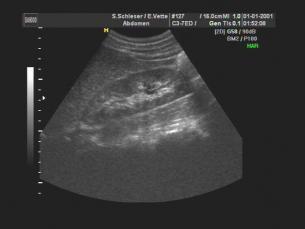

Bauchorgane:

Mit einem Schallkopf geringerer Auflösung aber größerer Übersichtlichkeit können Blutgefäße, Bauchspeicheldrüse, Gallensystem, Leber, Nieren, Milz, Prostata und Blase untersucht werden. Bei Magen und Darm ist die Aussagekraft dagegen nur eingeschränkt. Hier stehen andere Untersuchungen (Gastroskopie, Koloskopie, evtl. Röntgen) im Vordergrund.